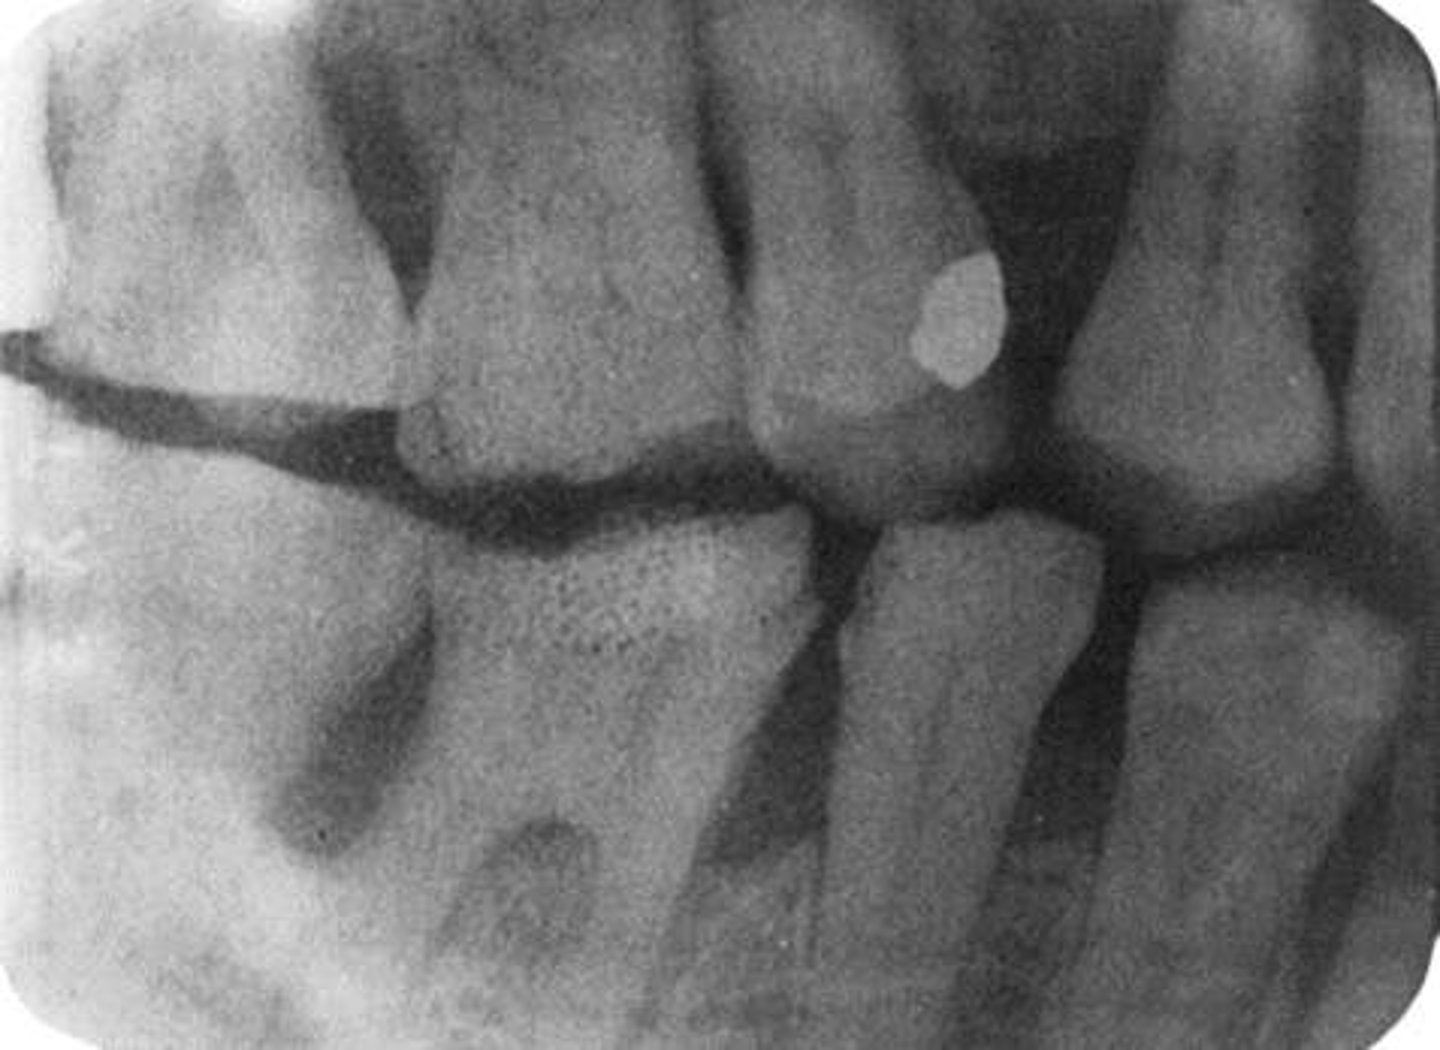

Overlapped interproximal contacts

Result from incorrect horizontal angulation; be sure to direct the x-ray beam through the interproximal regions.

<p>Result from incorrect horizontal angulation; be sure to direct the x-ray beam through the interproximal regions.</p>